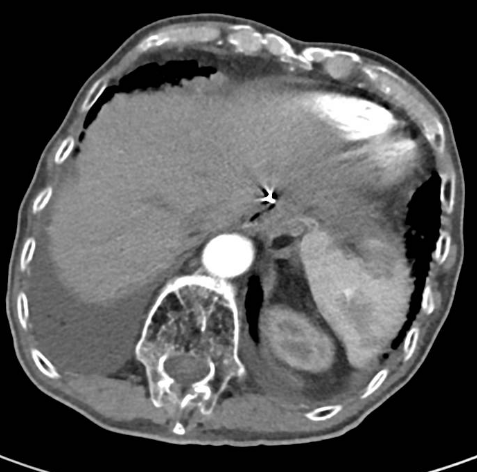

强化CT:1、符合胃部分切除术后,吻合口壁增厚伴食管下段扩张;2、胆囊结石:胆总管结合;3、肠淤张;4、前列腺增大;5、动脉硬化。

PET-CT检查:1、胃癌大部切除术后改变;肝左外叶近包膜下高代谢结节(于临近胃食管吻合口分界欠清),考虑肝转移。2、右肺中上叶多发结节伴代谢轻度增高;双肺间质纤维化;双肺泡性气肿;经根部气管憩室;贫血;动脉硬化;双侧胸膜增厚;右肺门及纵隔内多发淋巴结增生。

△ 2019.7影像学检查

2020-01-08复查腹部CT:与患者前片(2019-7-8)比较显示:食管胃吻合口区低密度病变范围较前缩小。所示腹部其余病变较前未见明显变化,双肺片状高密度影,双侧胸腔积液。

△2020.01腹部CT

2020-08-31复查腹部CT:与患者前片(2020-1-8)比较显示:所示腹部病变较前未见明显变化。双肺高密度影范围较前缩小。

△ 腹部CT 2020.08